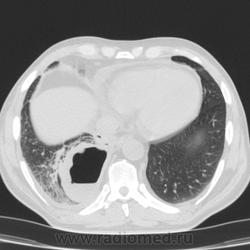

Здравствуйте, коллеги! Не откажите в помощи интерпретировать этот хаос в легких. После переохлаждения больной обратился за медиц помощью только через 1 месяц, в первые 2 недели была температура до 38*, сейчас после лечения самочувствие улучшилось, направлен на КТ контроль после лечения пневмонии. Подскажите, какой выставить диагноз?

Полость в нижней доле правого легкого, неправильной формы, с вовлечением и сдавлением бронхов, с уровнем жидкости. Отмечается утолщение костальной плевры с небольшим количеством жидкости. Не исключается инфекционная деструкция или новообразование правого нижнедолевого бронха, с ателектазом и деструкцией.

Дренированный абсцесс нижней доли справа.

Согласен с тем, что это - абсцесс(я бы даже сказал - абсцедирующая гангрена) нижней доли правого лёгкого.Коллега Nikolas, совершенно справедливо, характеризовал это состояние как промежуточное между абсцессом и гангреной.

Главное отличе абсцесса и гангрены не состояние(нет!И при абсцессе оно может быть тяжелейшим, со сдвигом лейкоцитарной формулы до миелоцитов, гектическими размахами температуры, тяжелейшей интоксикацией, даже с токсической острой почечной недостаточностью), а МОРФОЛОГИЯ. Абсцесс менее распространенный и всегда ограниченный. Гангрена - очень распространенная (вся доля, все легкое даже) и не имеет четких границ. Здесь - большая распространенность(вся доля), но есть четкая граница.